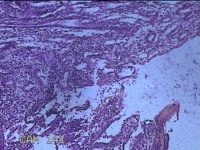

子宫腔内膜组织

性别

女

年龄

44岁

临床诊断

子宫异常出血、甲亢、轻度贫血

一般病史

阴道流血20天,加重1天。

标本名称

大体所见

灰白暗红色不规则碎组织3x2.8x0.3cm一堆。

图2

貌似增生反应子宫内膜。